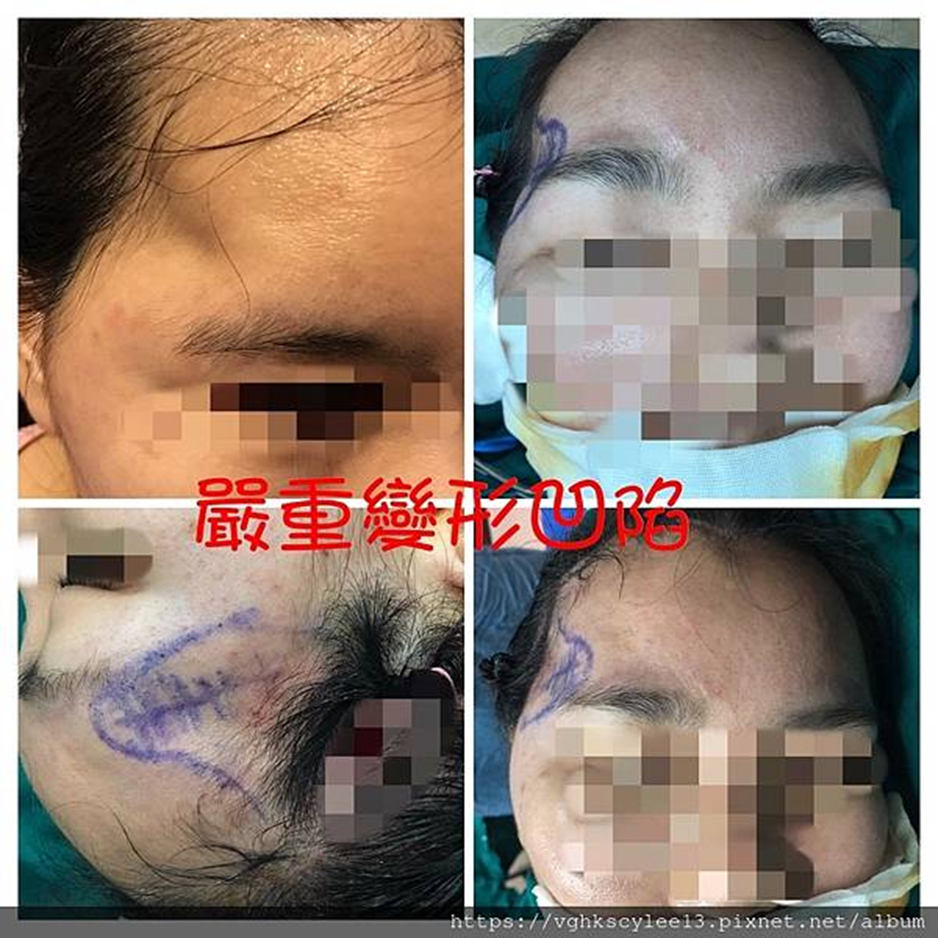

1. 注射填充——如玻尿酸或其他人工填充劑,但因為咀嚼肌的活動,這些材料會比其他部位更快吸水膨脹和變形及移位,容易造成不平整。可能出現凹凸、吸收、移位往往需要一再修補觸逐漸的饅化與走形。下圖3D電腦斷層掃描可見填充劑在組織纖維間隙的堆疊。凹凸不平是合理的,修補容易逐漸饅化。

sculptra(PLLA俗稱童顏針或長肉針,無法立即產生填補效果),注射效果緩慢且不穩定(無法預期),還必須持續壓揉避免併發症(過度生長成結節)。需要耐心和時間。下圖太陽穴筋膜因注射童顏針造成組織筋膜沾黏硬化,影響之後拉皮手術過程。

2. 注射自體脂肪–同樣因咀嚼肌活動,與脂肪細胞特性吸收率高,可能須多次注射。易發生不平凹凸(吸收不均或鈣化顆粒),再者脂肪太陽穴常造成頭大厚重感,求美者擔心的饅化😅(下圖)。讓臉型不夠精緻。

豐太陽穴凹陷的問題可以透過數種方式處理。注射美容雖然方便,卻存在一些風險和問題。比較嚴重副作用包括栓塞。